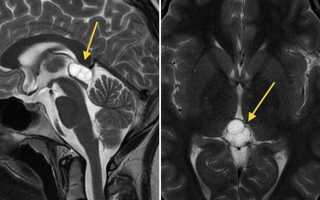

Еще раз напомним, что киста может существовать бессимптомно. Обнаружить ее удается при МРТ, которое проводится совершенно по другому поводу.

Диагностика кисты шишковидной железы головного мозга может включать проведение нейровизуализации, такой как МРТ или КТ, для определения размера и формы кисты. Еще одним методом диагностики может быть пункция кисты – взятие малого количества жидкости из кисты для анализа. Лечение кисты шишковидной железы может включать наблюдение без медикаментозного лечения или проведение хирургического вмешательства в случае необходимости.

?Для определения наличия кисты шишковидной железы головного мозга проводятся различные диагностические исследования. Они помогают уточнить диагноз, выявить размеры и характер кисты, а также оценить состояние окружающих тканей и органов. Для диагностики кисты могут применяться следующие методы:

| Магнитно-резонансная томография (МРТ) | Позволяет получить трехмерное изображение головного мозга и точно определить размеры и местоположение кисты. |

| Компьютерная томография (КТ) | Дает возможность получить поперечный срез головного мозга и выявить кисту. |